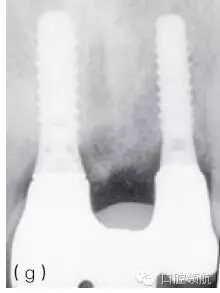

當(dāng)植入位置不佳不能以軟組織移植來(lái)挽救,而患者又要求達(dá)到良好的美學(xué)效果,除了取出種植體重新開(kāi)始之外,別無(wú)選擇。取出種植體后通常需要進(jìn)行骨增量,之后在正確位置上植入新種植體。對(duì)于局部骨增量,推薦引導(dǎo)骨再生(GBR)技術(shù),可同期或分階段進(jìn)行。外科方法的選擇主要取決于取出種植體時(shí)造成骨缺損的范圍和形態(tài)。任何時(shí)候,盡量在種植體植入同期行GBR,這時(shí)候一般是二壁骨缺損,如此可以避免患者接受額外的手術(shù)程序。然而,取出種植體導(dǎo)致的一壁骨缺損需要分階段的方式,首次骨增量采用自體骨塊移植加膠原膜覆蓋,5~6月后再植入種植體。這些治療需要患者和醫(yī)生的合作,通常可以獲得不錯(cuò)的美學(xué)效果(圖8.26a~g)。

圖8.26 (a)一個(gè)非常嚴(yán)重的病例:上頜前牙區(qū)植入3顆種植體。首先,考慮到美學(xué)效果,應(yīng)該只在8號(hào)和11號(hào)位點(diǎn)植入2顆種植體;其次,8號(hào)種植體冠向植入位置不佳伴肩臺(tái)外露。3顆種植體都需要取出。(b)種植體取出術(shù)中應(yīng)做避開(kāi)齦乳頭的小切口,盡量減少創(chuàng)傷。(c)翻開(kāi)黏骨膜瓣后清楚可見(jiàn)唇側(cè)骨缺損。在種植體鄰面小心去骨,盡量減少唇側(cè)去骨。(d)取出3顆種植體后的臨床情況。骨缺損處清創(chuàng),膠原塞填充。(e)手術(shù)完成,初期傷口關(guān)閉需達(dá)到軟組織完整覆蓋缺牙區(qū)。6~8周后種植體植入并同期行GBR。(f)植入2顆種植體和局部GBR骨增量治療3年后的效果。用低替代物含量的骨充填物(去蛋白小牛骨礦化基質(zhì))行橋體區(qū)域垂直骨增量。(g)3年隨訪檢查的X線片。新植入的2顆種植體顯示出穩(wěn)定的種植體周骨水平,尤其在橋體區(qū)域。